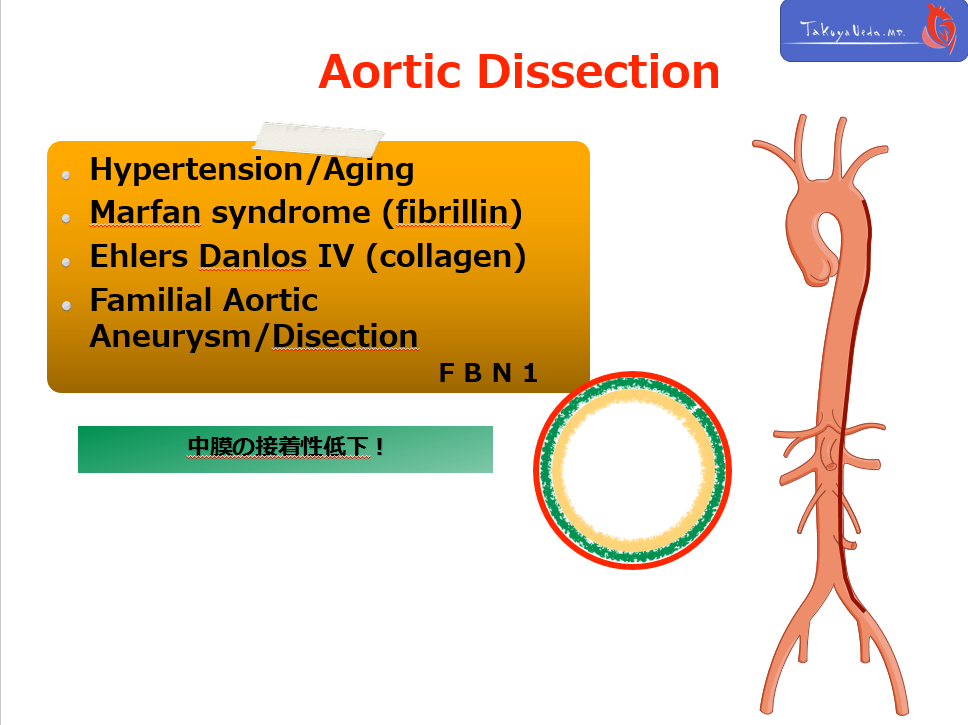

大動脈解離の背景因子としては、まず高血圧があげられますが、これに加えてMarfan症候群やEhlars Danlos症候群など、いくつかの結合組織疾患が有名です。

近年では、家族性発生を示す大動脈解離の存在が広く知られるようになりました。Marfan症候群にも共通する F B N 1 geneの変異に注目が集まっており、近年では、大動脈解離を遺伝的素因を背景とした系統疾患ととらえる動きもあります。(クリック)